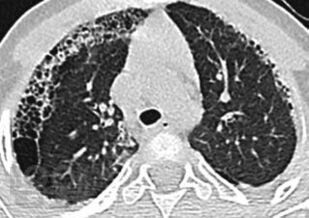

Сборник включает вызвавшие наибольший интерес аудитории лекции и доклады на различных научно-практических конференциях в 2020-2021 гг. по актуальным проблемам пульмонологии и аллергологии детского возраста, таким как: современные методы диагностики и лечения, острые и хронические инфекционно-воспалительные и аллергические заболевания органов дыхания, муковисцидоз, туберкулез органов дыхания, COVID-19, а также различные другие информационные материалы. Ежегодник адресован практикующим детским пульмонологам и аллергологам.